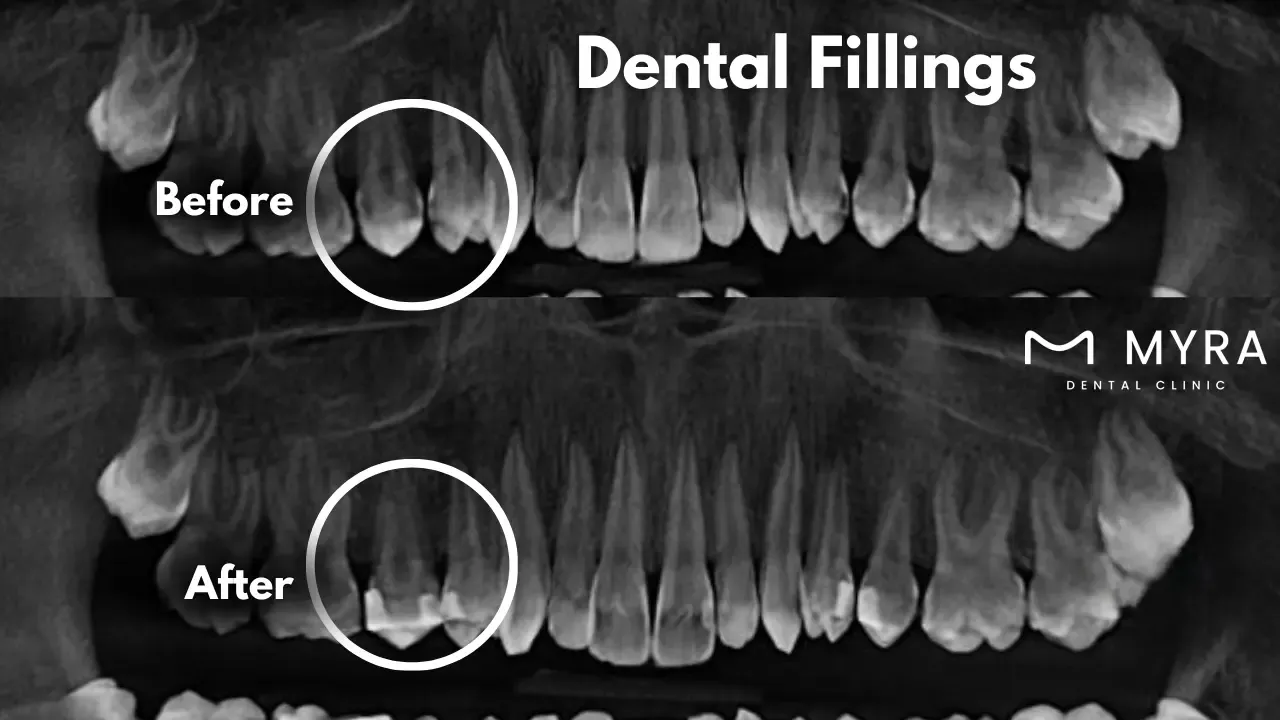

The dental filling procedure involves a series of steps. The dentist first takes X-rays and examines the tooth before beginning the dental filling process. A local anesthetic is used to make the area around the damaged tooth numb. The tooth's decaying area is extracted by the dentist using a drill or laser. The cavity is cleansed to get rid of any leftover bacteria or debris. Layers of the selected filler material are applied. Each layer is molded and hardened with a specific light for composite fillings, while for other materials, it is left to set. The dentist polishes it to ward against discoloration and premature wear after the filling is inserted.

Dental fillings remove the damaged material from the tooth and fill the resulting cavity, preserving the structure and functionality of the tooth. The dentist examines the tooth and frequently uses X-rays to assess the degree of decay. The area is made numb by local anesthetic. A dental drill or laser removes the tooth's decaying area which stops future deterioration by ensuring all contaminated material is removed. The cavity is carefully cleaned to remove leftover bacteria and debris once the decay is eliminated. The dentist chooses a filling material such as amalgam, composite resin, gold, or porcelain depending on the location and degree of the cavity. The selected material is inserted into the cavity after cleaning. The filling is contoured to fit the tooth's natural curves to guarantee a proper bite. A specialized laser is utilized to harden the material used in composite fillings. The filler is polished to provide a natural appearance and feel and to smooth down any sharp edges.